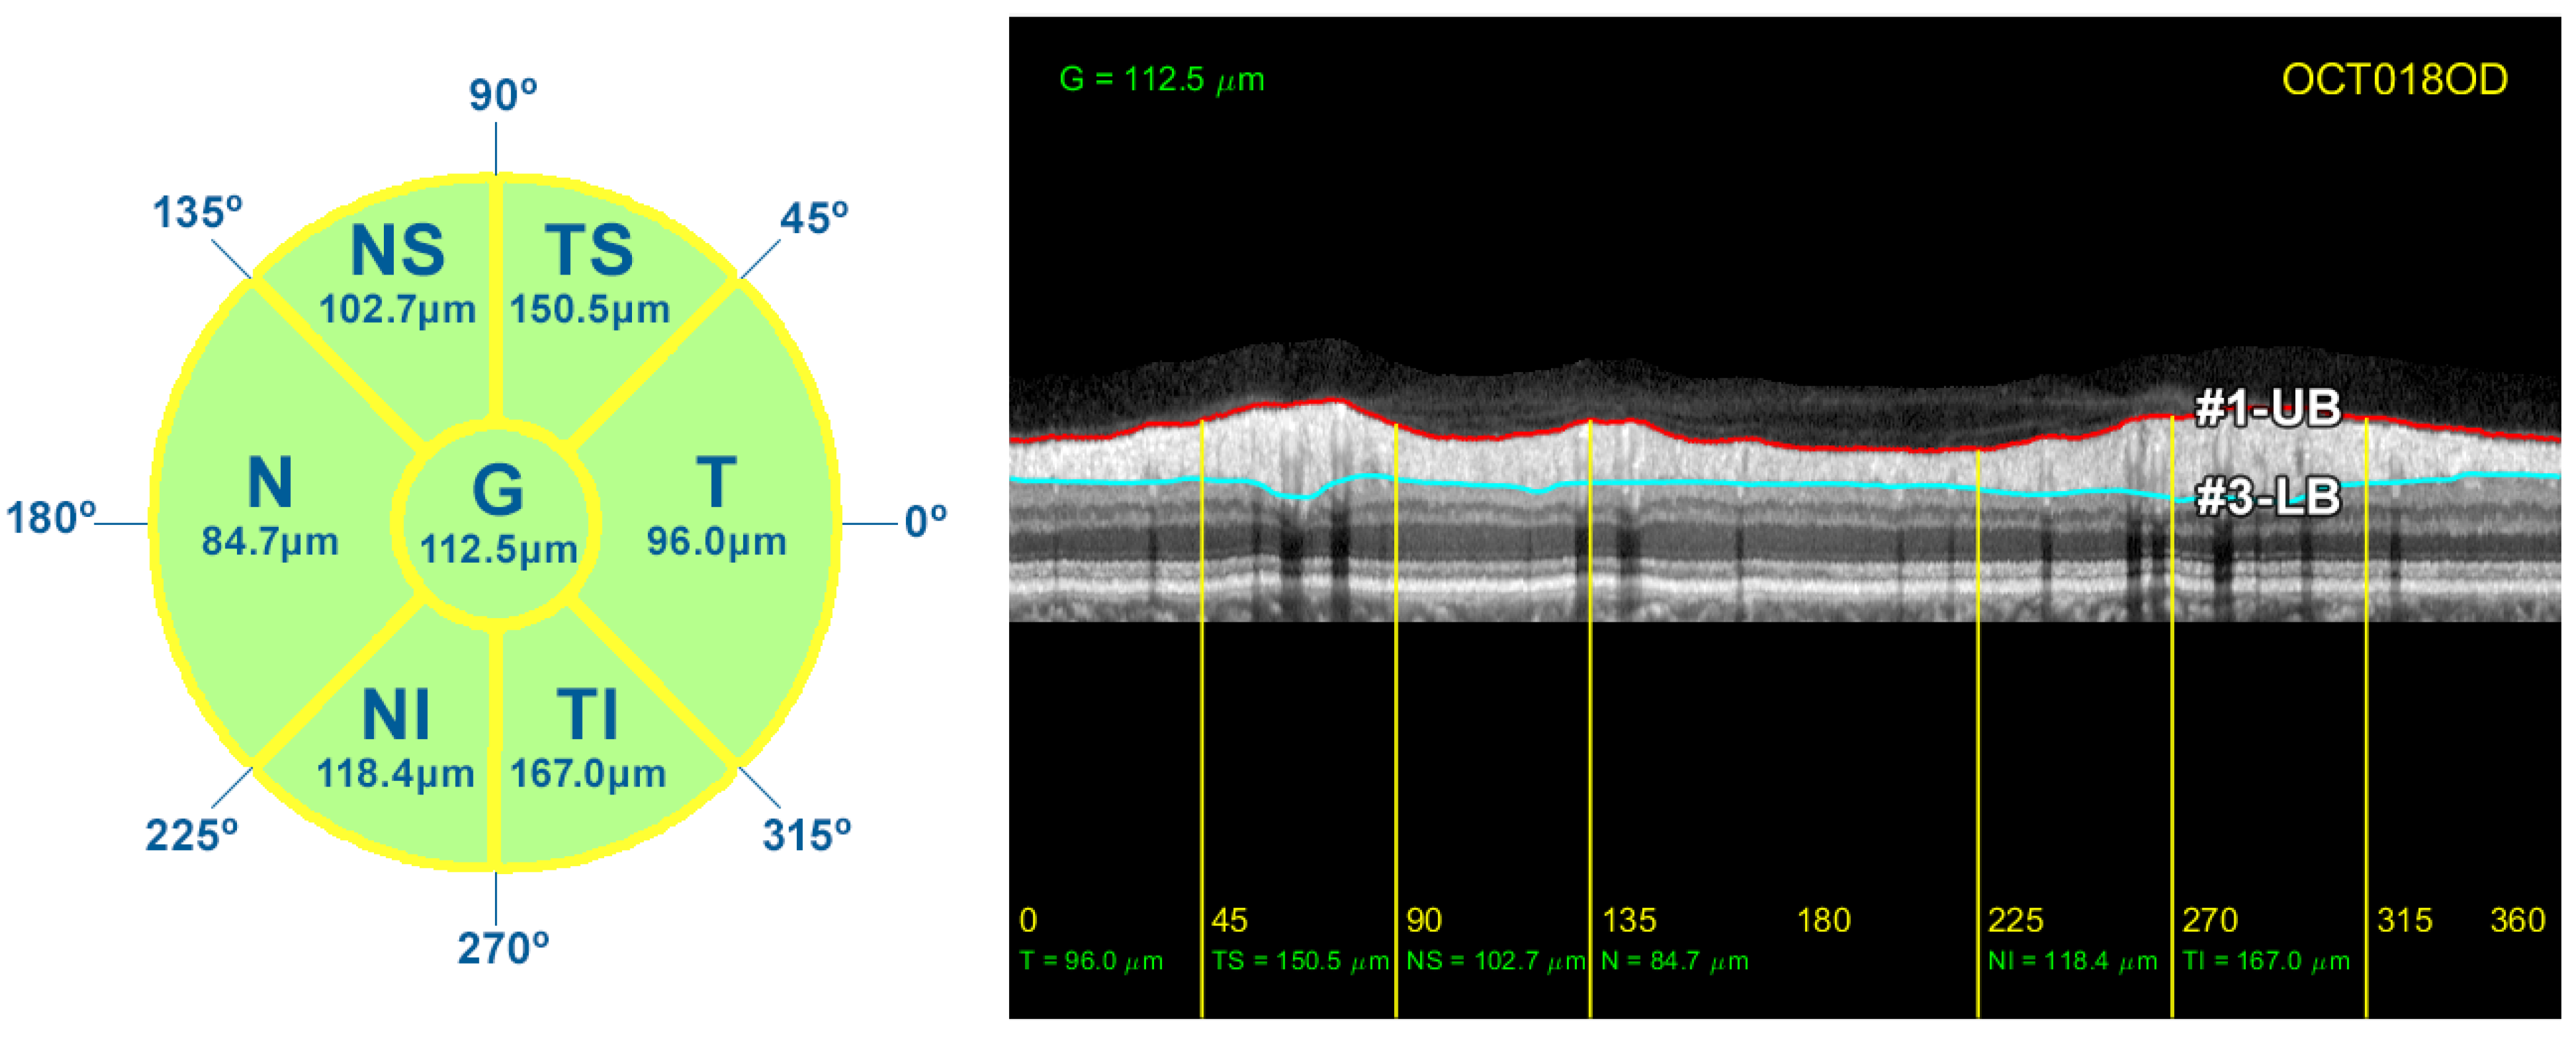

As described in Section 1, the thickness of the RNFL and GCL is important for monitoring the progression of ocular diseases such as glaucoma. In order to compare the results provided by the proposed method with the measurements given by the OCT device, the circumpapillary RNFL thickness was averaged by sectors (T, TS, NS, N, NI, and TI), and the global mean value was also calculated (G). The thickness of the RNFL was calculated by simply subtracting the position of contours #1-UB and #3-LB, resulting in a vector w with the thickness of the layer at each x-coordinate of the image I. The correspondence between the x-coordinate and the polar coordinate of the analysis circumference is detailed in Table 2 and depicted in Figure 3. This vector w allowed us to calculate the average value of the RNFL thickness in all the different sectors of the eye. Figure 14 displays the resulting measurements for the OCT image used in the description of the method.

Figure 14.

RNFL thickness measurements for each sector of the peripapillary circumference. On the left, diagram detailing the value of the average thickness of the RNFL in each sector of the eye. On the right side, representation of the borders #1-UB and #3-LB, and the average RNFL thickness in these sectors.

Screenshot provided by the Spectralis software version 6.9.4.0. From left to right and top to bottom: Retinal fundus photography centered on the optic disc (the yellow circle indicates the location of the peripapillary B-scan, which is shown on the right with the segmentation of the RNFL); 2D peripapillary B-scan OCT on Cartesian coordinates; estimated mean values for RNFL layer thickness for the temporal (T), temporal superior (TS), nasal superior (NS), nasal (N), nasal inferior (NI), and temporal inferior (TI) sectors, as well as the overall mean (G); rectified outline of the RNFL with estimated thickness and reference values according to the database European Descent (2009).

The OCT images used in this work have a resolution of 768 × 496 pixels with a z-scaling of 3.87 µm/pixel and a bit depth of 8 bits/pixel in grayscale. The diameter of the peripapillary OCT circumference can be adjusted according to the size of the patient’s eye, varying the horizontal resolution of the OCT accordingly. For instance, a circumference diameter of 3.7 mm corresponds to a x-scaling of 15.21 µm/pixel. Note that only the z-scaling was used for this work, since the main goal is to determine the vertical thickness of the RNFL in the OCT image. The top left of Figure 2 shows the circular tracing of the SLD beam on the retinal fundus image of the eye. This analysis circumference is positioned over the center of the optic nerve (or papilla) as depicted in the figure.